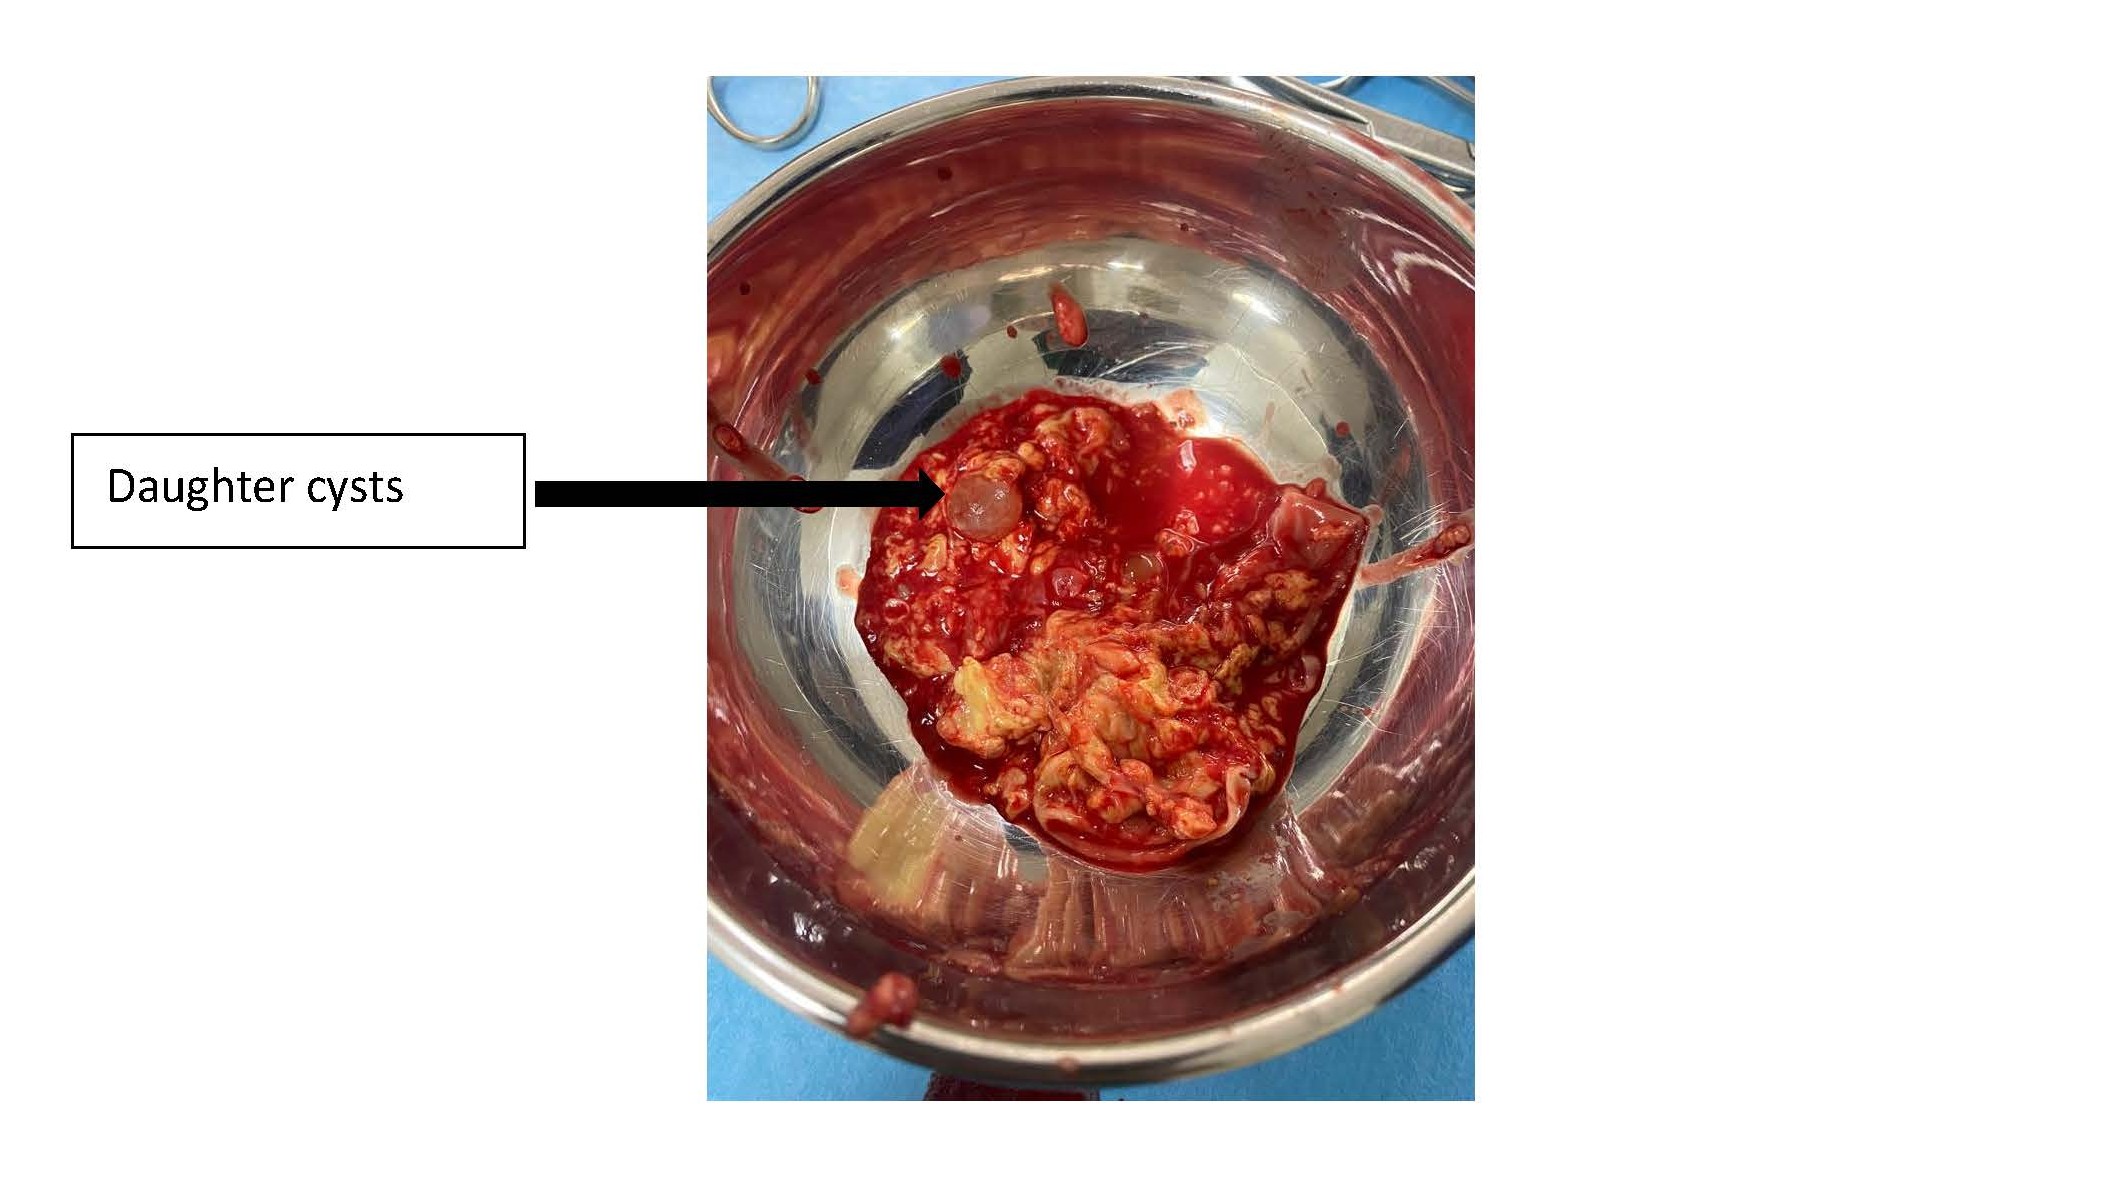

In order to study the ratios of the mass more closely, an MRI scan was carried out, which revealed a right paramedian intermuscular fluid formation located between the erector spinae muscles on the inside and the trapezius on the outside, with a fusiform shape measuring 96 mm in height and 52 x 30 mm in larger dimensions in the axial plane. This formation has a multiloculated appearance and does not show any significant enhancement after injection of gadolinium. This mass initially suggests a hydatid origin (Figure 1). The hydatid serology was positive, and the TAP CT did not reveal any other sites of disease. The patient had monobloc excision of the cyst with no intraoperative rupture (Figure 2 and Figure 3) and the postoperative course was uncomplicated. Histological examination confirmed the diagnosis of a muscular hydatid cyst. At the 6-month and 1-year follow-up, clinical, biological, and ultrasonographic evaluations revealed no evidence of local or visceral recurrence.

Figure 3. Multivesicular content observed after cyst incision.